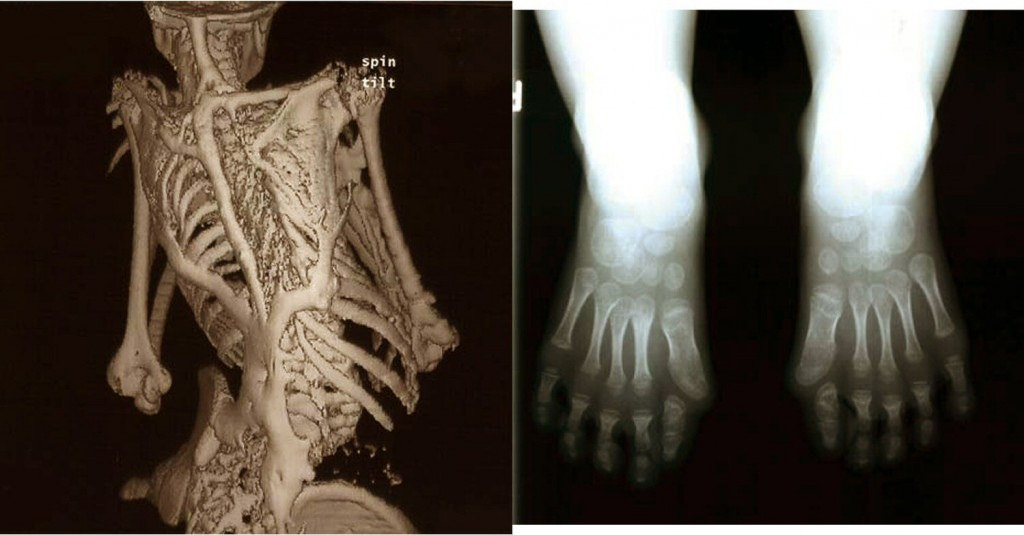

Превратиться в кости

Превратиться в кости 110 фото